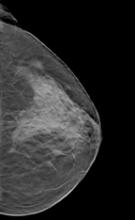

Patients are noticing the difference since Rye Radiology implemented 3D mammography more than two years ago, in 2012. Some are amazed they no longer need extra views. Some are grateful their 3D exam found that suspicious lesion when it was small and easier to manage. At least one patient credits the 3D exam with saving her life.